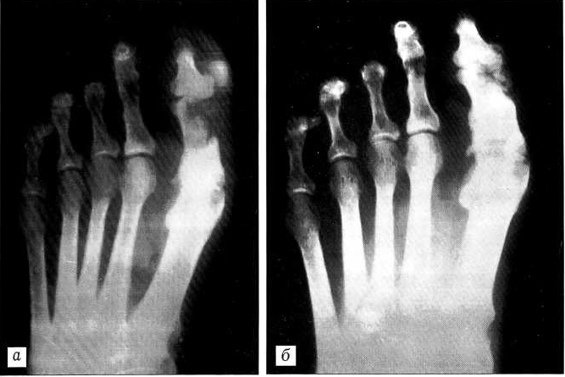

Рентгенограммы левой стопы больной Н.: a — до лечения, б — после лечения.

госпитализирована для определения дальнейшей тактики лечения. В анамнезе обращает на себя внимание тот факт, что похожим заболеванием страдает бабка больной по материнской линии. При осмотре стоп: дистальные фаланги 11—IV пальцев справа и III пальца слева отсутствуют. На левой стопе I палец умеренно отечен, кожные покровы гиперемированы, на подошвенной поверхности определяются рубцовые изменения (закрывшийся свищ). При пальпации отмечается локальная гипертермия в границах гиперемии, умеренная болезненность по подошвенной поверхности, снижение всех видов чувствительности I пальца левой стопы. Объем движений в первом плюснефаланговом суставе умеренно ограничен из-за отека. Периферическая пульсация сохранена. Рентгенологически определяется очаг деструкции в основной фаланге I пальца размером 2x1x1 см с нечеткими контурами, негомогенный (см. рисунок, а). Выполнено исследование на чувствительность к антибиотикам (мазок из зева чувствителен к левомицетину).

После проведенного лечения отек I пальца левой стопы спал, боли при ходьбе не беспокоят, температура нормализовалась. Палец удалось сохранить. Рентгенологически определяются признаки консолидации, отрицательная динамика отсутствует (см. рисунок, б).